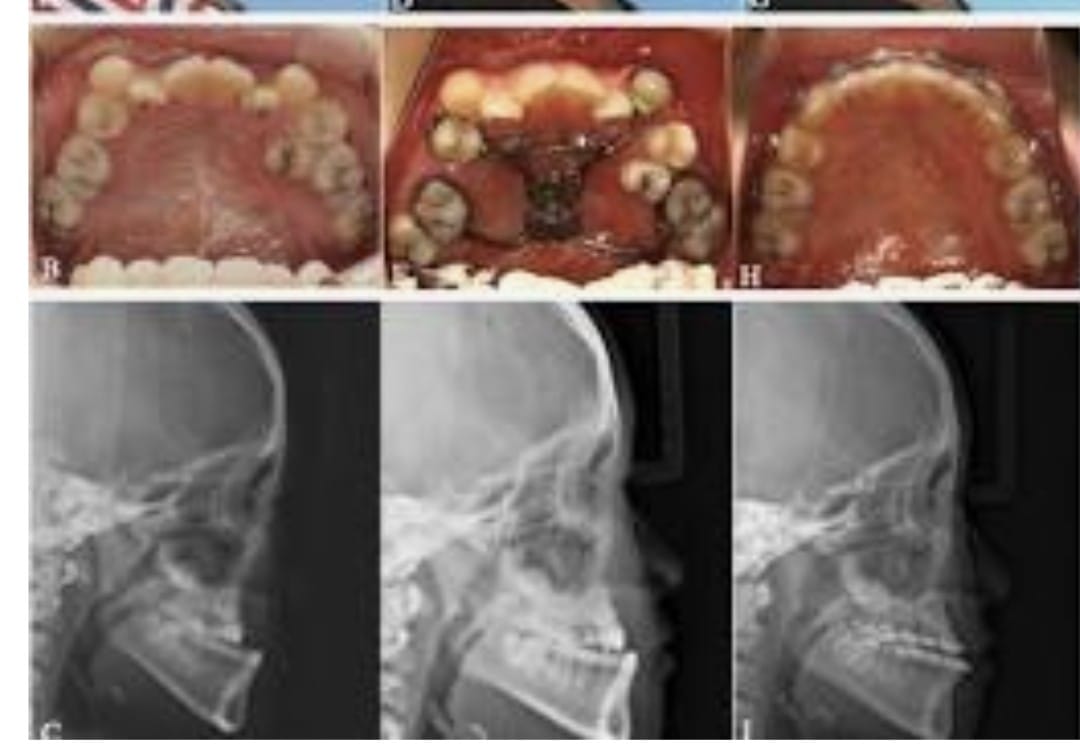

Maxillary prognathism is a dental and facial condition in which the upper jaw extends forward more than normal in relation to the lower jaw. This condition can affect the overall balance of the face and may lead to difficulties with proper bite alignment, chewing, and speech. In many cases, maxillary prognathism develops due to genetic factors, abnormal jaw growth, or developmental conditions that affect the structure of the facial bones.

Patients with maxillary prognathism often experience an excessive overlap of the upper teeth over the lower teeth, commonly referred to as an overbite. This misalignment can sometimes lead to discomfort in the jaw, uneven wear of teeth, and difficulties in maintaining proper oral hygiene. Early diagnosis is important in order to determine the most suitable treatment approach and prevent further complications. Treatment for maxillary prognathism depends on the severity of the condition and the age of the patient. In mild cases, orthodontic treatments such as braces or aligners may help correct the alignment of the teeth. However, in more severe cases where the jaw structure is significantly affected, orthognathic surgery may be recommended. This surgical procedure repositions the upper jaw to achieve better facial balance and proper bite alignment. Modern dental and surgical techniques allow specialists to carefully plan and perform these procedures with high precision. With proper treatment and follow-up care, patients can achieve improved jaw function, better facial harmony, and a more confident smile. Maxillary prognathism treatment plays an important role in restoring both functional and aesthetic aspects of oral health.

III. Types of Maxillary Jaw Surgery

- Le Fort I Osteotomy: A procedure that separates the upper jaw from the rest of the facial bones, which facilitates repositioning it forward, backward, superiorly (upward), or inferiorly (downward), thereby creating a better facial appearance.

- Pre-surgical Orthodontics: Often needed before the actual surgery takes place. Imaging: X-rays and CT scans are required.

- Planning: Virtual surgical planning is performed on a computer, along with model surgery.